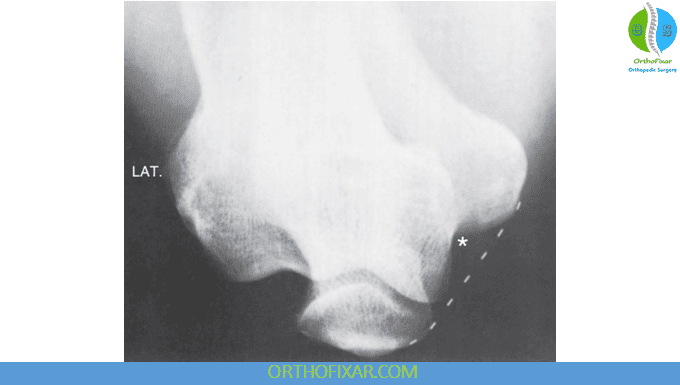

- Instability/trauma clues:

- Dislocations (posterior most common)

- Radial head dislocation may cause an impaction defect of the capitellum (Hill-Sachs–type lesion of the elbow).